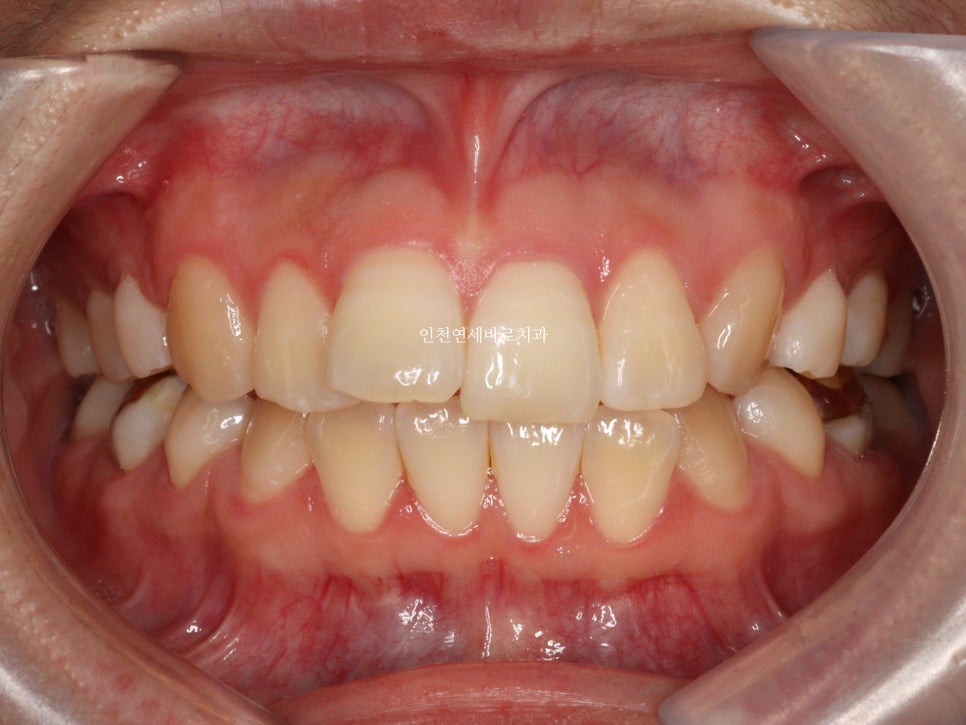

변화모습입니다.

약 3개월의 변화모습입니다.

그리고 치료가 마무리 된 후의 모습입니다.

부분교정으로 앞니만 철사를 붙여서도 비슷한 효과를 볼 수 있었을지 모릅니다.

하지만 치아의 삭제가 많은 양 동반되지 않았다면 앞니가 분명 뻗쳐나왔을것입니다.

하지만 인비절라인은 전체교정에 준하는

치아와 주변조직에 무리가 되지 않는 범위에서의 확장을 만들어낼 수 있어

앞니의 뻗침을 최소화 할 수 있는 장점이 있습니다.

위 환자분의 재교정 치료기간은 약 7개월입니다.